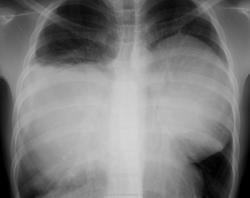

ID: 8918 Mediastinal teratoma Dr Frank Gaillard - 9 Mar 2010 Chest x-ray in a child demonstrates a rounded mass projecting over the m...

ID: 13309 Mediastinal teratoma Dr Sudarshan Deshmukh - 25 Mar 2011 Chest X-rayshows Lt sided homogeneous opacity involving the mid zone ,lo...